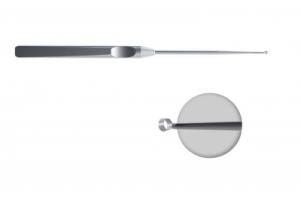

- ID: 0052237

- Артикул: AS-01401-1

Ножницы эндоскопические с одной подвижной браншей (клювовидные, левые)

- ID: 0052238

- Артикул: K-0304E

Инструмент для расширения полостей и сепарации ткани (угловой 90 град.)